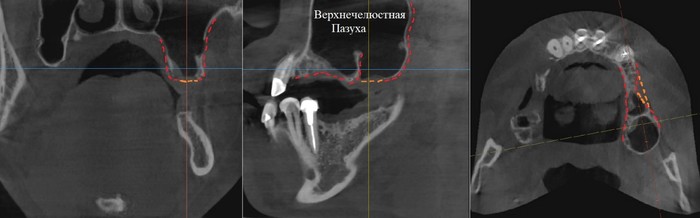

Фрагмент компьютерной томографии (вид сбоку):